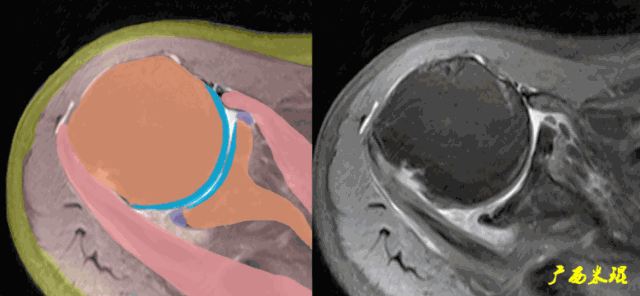

肩关节MRI检查扫描平面

(1)斜冠状位:平行于冈上肌腱长轴,主要评估冈上肌。

(2)斜矢状位:垂直于冈上肌长轴,观察肩峰形态及喙肩弓,观察肩袖4个组分的短轴断面。

(3)平行于关节盂/垂直于盂肱关节,主要评估盂唇,同时兼顾肩胛下肌、冈下肌及小圆肌。